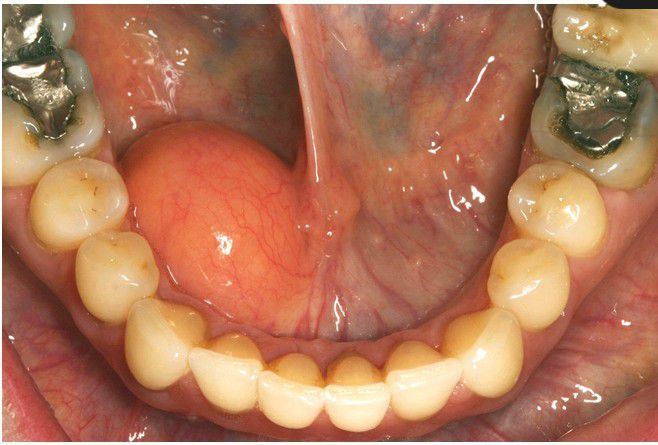

Lipoma

Soft, yellow nodular mass in the floor of the mouth.